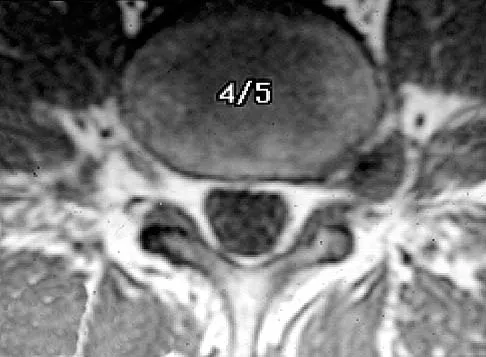

A 42-year-old man has had left lower extremity pain in an L5 radicular pattern for the past 6 weeks. He denies significant axial low back pain. History reveals that he underwent an L4-5 diskectomy with successful relief of similar pain 5 years ago. Which of the following imaging studies would offer the greatest amount of information?

Explanation